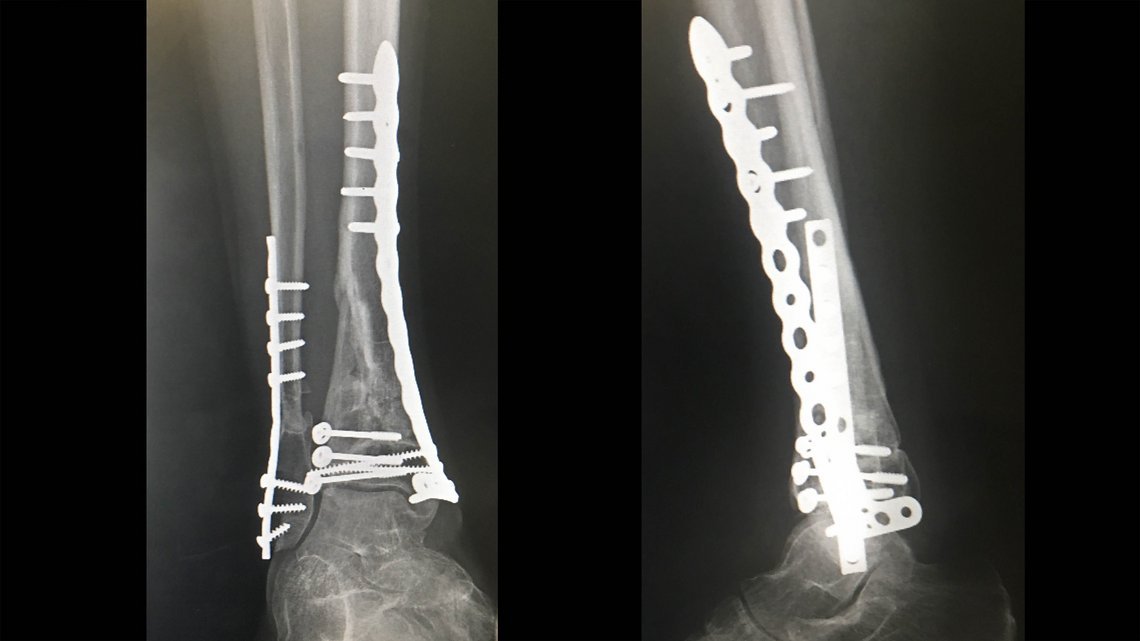

Sascha Bamberg hat sich im vergangenen Jahr sein rechtes Schien- und Wadenbein knapp über dem Sprunggelenk in viele Teile zertrümmert. Passiert ist es auf Madeira, als er Brendogs Deathgrip-Line gefahren ist. Er ist einen Sprung übersprungen und damit die Kurve zum nächsten Kicker verfehlt. Normalerweise sollte man sich auf der wunderschönen kleinen Insel nicht zerstören, denn es gibt keinen Hubschrauber und nur ein offizielles Krankenhaus.

Nach einer Inselrundfahrt im Krankenwagen und der Flucht aus dem offiziellen Krankenhaus in die Privatklinik hat der beste Doc auf Madeira – Paulo Sales, ebenfalls passionierter Mountainbiker – das Knochenpuzzle in Saschas Bein mit zwei Platten und 18 Schrauben gelöst.